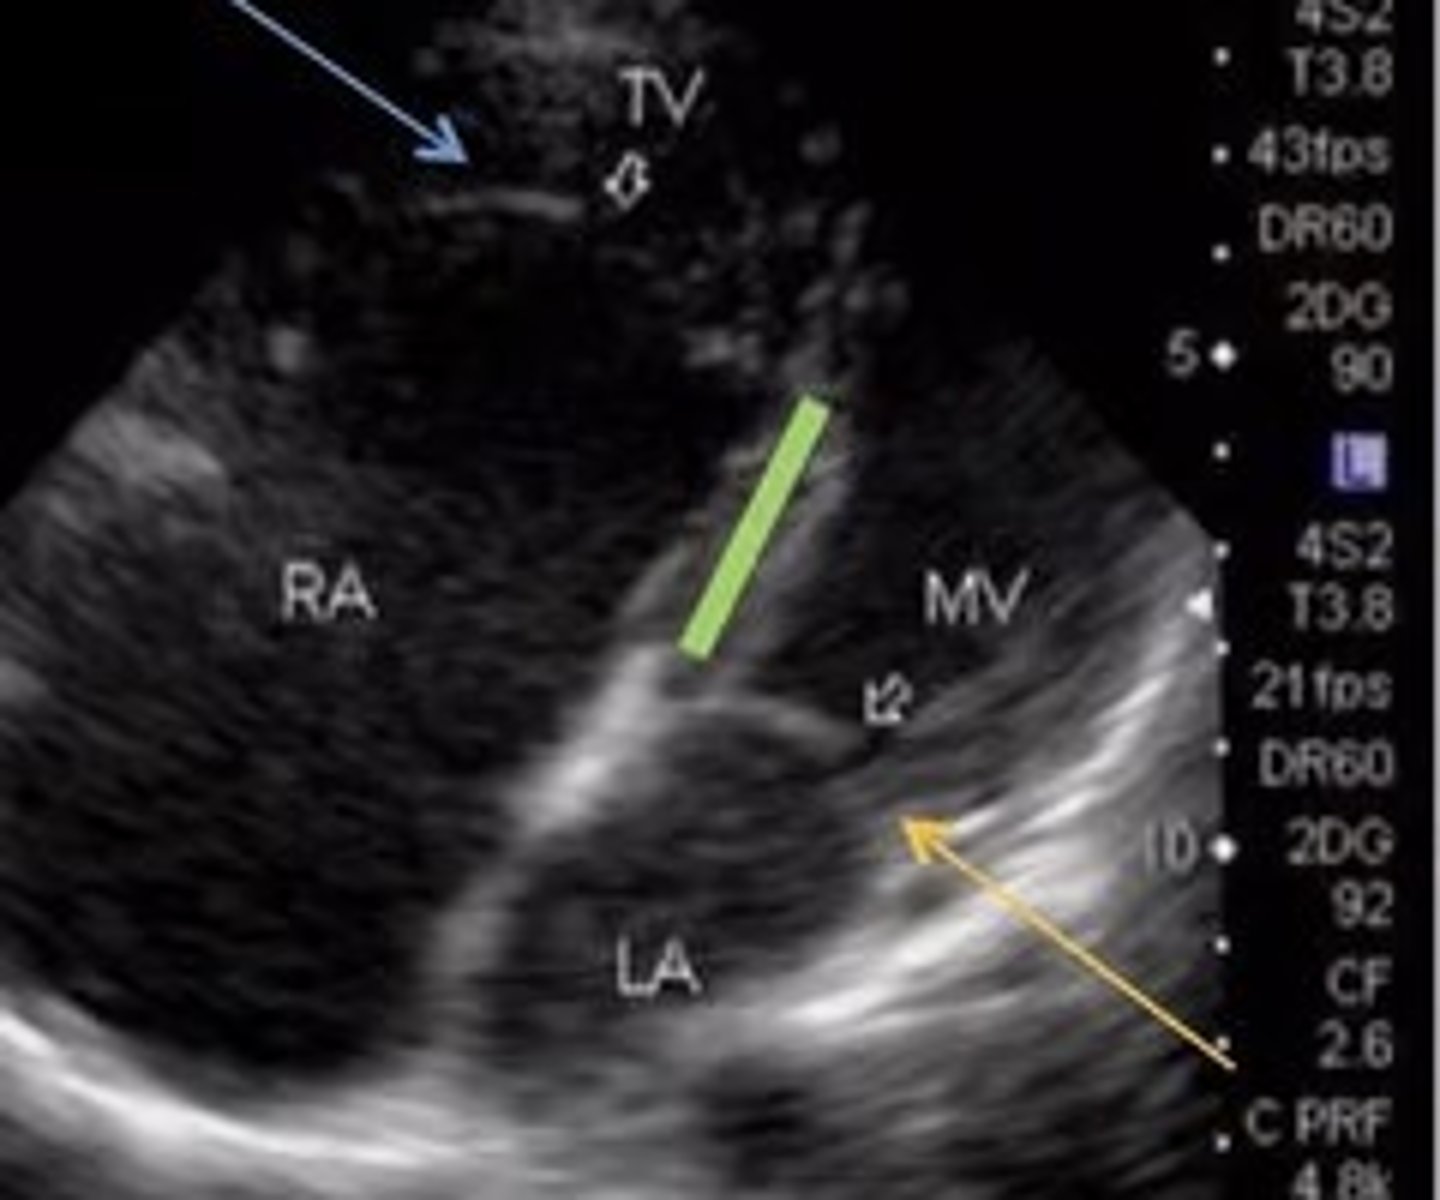

Ebstein's Anomaly

Best seen in 4 Chamber

Apical displacement of tricuspid valve -> TV is lower than it should be

ASD

Best seen when IAS is perpendicular to sound beam

Hole in atrial septum